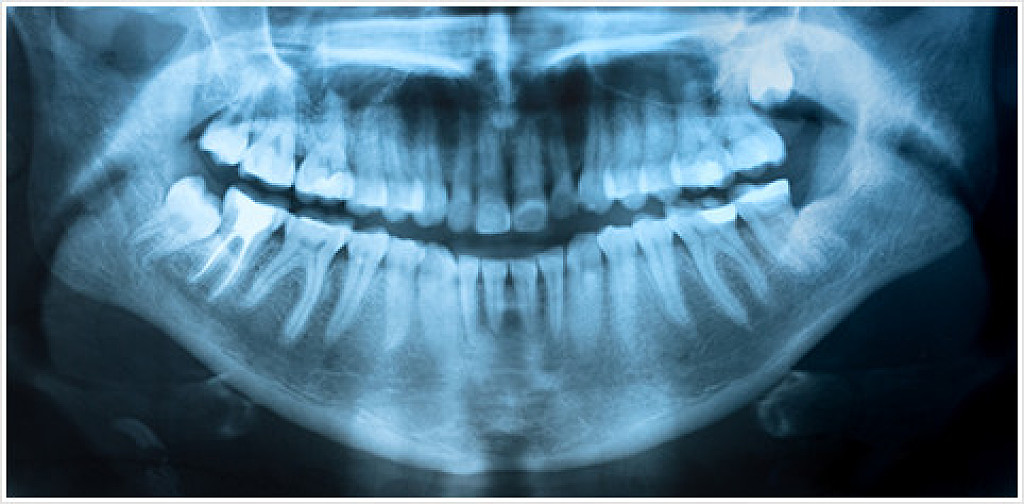

X-rays are a standard tool in the dental industry that we use to identify issues in the teeth, surrounding tissues, and jaw that would either be hard to see or hidden from a routine visual examination.

Some examples of problems we can spot with X-rays include tooth decay around restorations, deep cavities, jawbone infections, gum disease, abscesses/cysts, developmental abnormalities, and some types of tumors.

Chun Family Dentistry uses digital X-rays, because they have numerous benefits over their conventional counterparts. Digital X-rays don’t require any chemical processing, which means we get images faster and it’s easier on the environment. They also emit much less radiation, keeping you safe in our care!